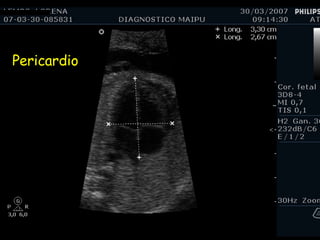

Pericardio